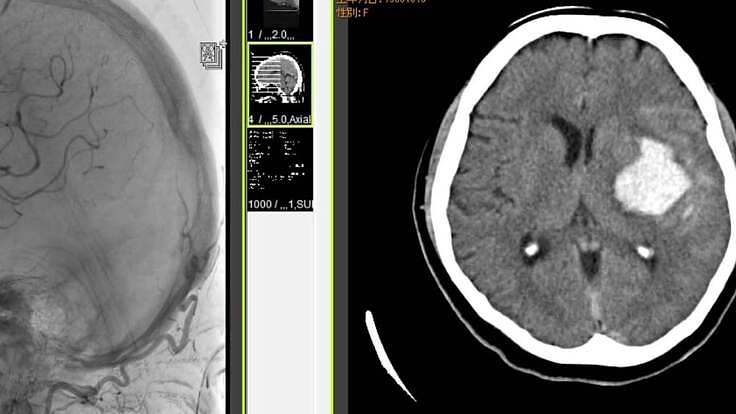

2017年10月に私の妻は突然脳出血に襲われて救急搬送され,何とか意識は戻したものの記憶と言語を失うと共に右半身が麻痺した。私と妻,そして1匹のネコだけの家族は,それまでシンプルライフを享受してきたが,妻の発病でその生活は一変した。すべての家事と看病・介護を私が担当することになり,私はそれまで続けてきた社会的な活動をすべて中止して,妻の看病と介護に専念し,この状態を今なお継続中である。

救急外来診察を受け,CT で脳を調べたところ,出血等の問題はなく,前年の脳出血の後遺症の一つとしての痙攣ということで,薬を処方されて直ちにタクシーで帰宅となった。